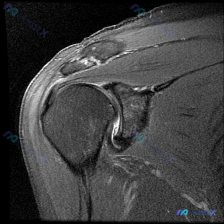

这是踝关节MRI-T2序列矢状位图像,核心问题是“影像中可以看到什么?提示软组织积液”。

- 前踝隐窝(胫骨远端前缘与距骨颈部之间)可见类圆形显著T2高信号,提示大量关节积液,不排除滑膜增厚

- 后踝及距下关节周围可见少量液体样高信号

- 距骨体部距骨穹窿处局部软骨下信号不均,性质待定,需排除软骨下骨髓水肿或骨软骨损伤

- 足底筋膜附近、距下关节周围可见条索状、点状高信号,提示局部软组织水肿或滑膜炎